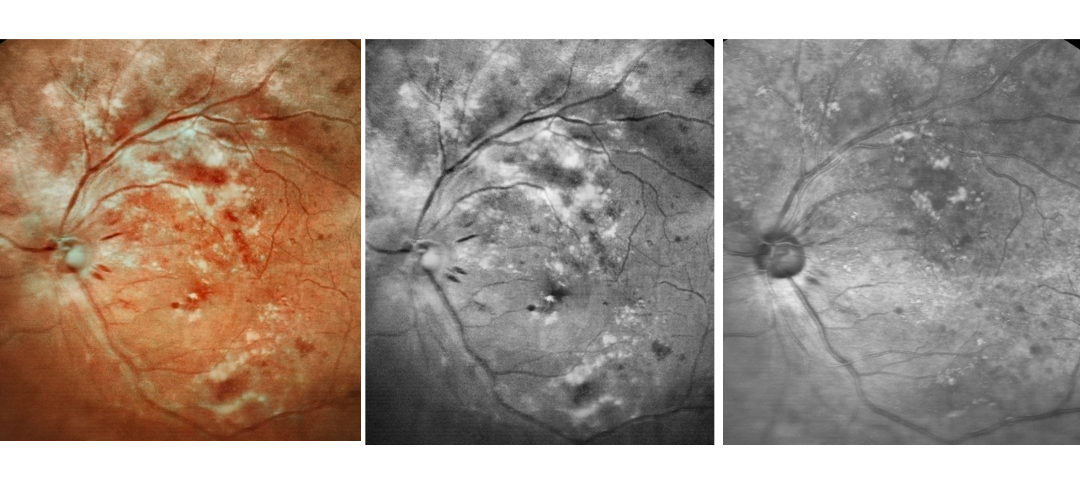

Scanning Laser Ophthalmoscope Obtain Retinal Layer and Choroidal Layer

Our scanning laser ophthalmoscope uses multi-wavelength laser scanning to penetrate the fundus, capture details of the retinal and choroidal layers, and obtain high-definition fundus images.

Fundus Cases Display

Our SLO makes fundus examination easier for you, capturing ultra-clear and wide-angle images of the retina and choroid, and then synthesizing color fundus images to present a rich picture of the fundus status.

Diabetic retinopathy: bleeding and microvascular lesions

Diabetic retinopathy: bleeding, exudation, and post-photocoagulation

Diabetic retinopathy: bleeding and exudation

Diabetic retinopathy: bleeding, exudation and choroidal vascular abnormalities

High blood pressure, venous obstruction, and bleeding